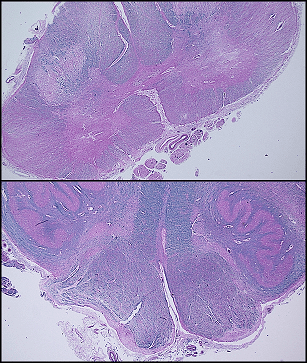

Caption: Amyotrophic lateral sclerosis (autopsy) Top. Combined H&E and LFB staining: Spinal cord with pink (loss of blue LFB staining) lateral columns secondary to axonal in descending cortical spinal tracts. Bottom. Combined H&E and LFB staining. Pyramids demonstrate slightly more pink staining corresponding to mild axonal loss in the region.